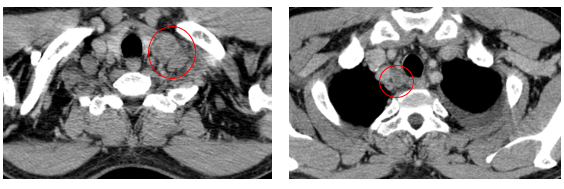

-         Chụp cắt lớp vi tính lồng ngực (08/2025): Khối rốn phổi trái ôm quanh nhánh phế quản thùy dưới trái kích thước 28x26mm, dày tổn chức kẽ vách liên tiểu thùy và nhiều nốt đặc lan tỏa khắp nhu mô, đường kính <7mm. Màng phổi trái có vài nốt đặc ngấm thuốc nốt lớn nhất kích thước 17x15mm  Khoang màng phổi trái có dịch dày 54mm. Nhiều hạch to trung thất, rốn phổi hai bên và hố thượng đòn có hoại tử trung tâm, hạch lớn nhất kích thước trục ngắn 22mm.

Hình 01: Nhiều hạch to trung thất, rốn phổi hai bên và hố thượng đòn có hoại tử trung tâm, hạch lớn nhất kích thước trục ngắn 22mm

-         Chụp cắt lớp vi tính lồng ngực (11/2025): Màng phổi vùng rốn phổi trái dày,dày tổ chức kẽ vùng ngoại vi đáy phổi hai bên. Màng phổi trái có vài nốt đặc ngấm thuốc nốt lớn nhất kích thước 17x15mm. Khoang màng phổi hai bên không có dịch – khí (Tổn thương giảm đáng kể so với phim chụp 08/2025). Trung thất, rốn phổi hai bên, hố thượng đòn trái có vài hạch, hạch lớn nhất kích thước 12x6mm. Vài nốt đặc xương rải rác thân đốt sống, các cung xương sườn hai bên.

Hình 07: Hạch thượng đòn trái giảm đáng kể kích thước, từ 22mm còn 7mm sau điều trị.

Hình 10: Không còn thấy tổn thương hạch trung thất nhóm 2 sau điều trị